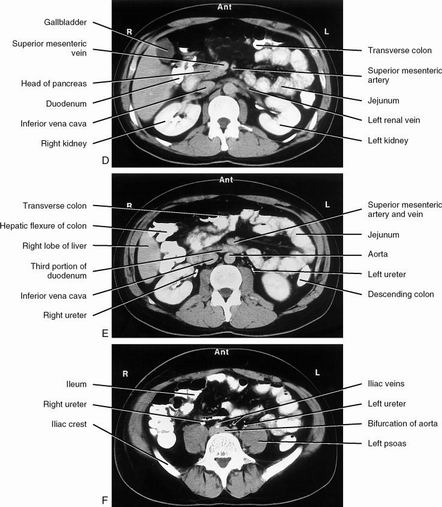

| Arterial phase & portal venous phase | |